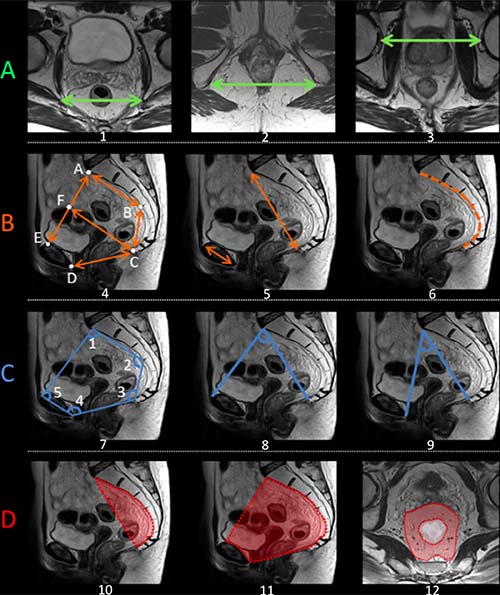

Pelvimetry was realized on the pretreatment MRI according to previously published criteria providing transverse, sagittal, angles, and surface measures [10, 11, 28–31, 61]. This approach produced 26 individual pelvimetric values describing the width, depth and angles of the lesser pelvis for each patient [29] (Figure 2). The surface was calculated in cm2 between different reference points of the pelvis [31]; the rectal surface and the mesorectal surface (horizontal plane) were evaluated at the level of the junction between the high and mid-rectum and the mid- and low rectum. Surface measures were made perpendicular to the rectum axis. In addition, 4 derivate measures were taken [10, 11].

Figure 2: Schematic representation of the main pelvimetric measurement on the pretreatment MRI. (A) Transverse measures: 1) Interichiatic spinous distance; 2) Intertuberous distance; 3) Interacetabular distance. (B) Sagittal measures: 4) AB: S3 to promontory distance; BC: S3 to coccyx distance; CD: Pubic symphysis to the tip of the coccyx distance (pelvic outlet length); AE: Promontory to pubic symphysis distance (pelvic inlet length); CF: mid-inlet length (pelvic depth); 5) Promontory to coccyx distance and pubic tubercle height; 6) Length of anterior sacro-coccigeal curve. (C) Angles: 7) Angle 1: superior anterior pubis – sacrovertebral angle – mid-S3; Angle 2: sacrovertebral angle – mid-S3 – coccyx; Angle 3: mid-S3 – coccyx – inferoposterior pubis; Angle 4: coccyx – inferoposterior pubis – superior anterior pubis; Angle 5: inferoposterior pubis – superior anterior pubis – sacrovertebral angle. 8) Promontory to the top of the pubic symphysis angle; 9) Promontory to the lowest tip of the public symphysis angle. (D) Surface measures: 10) Surface of the sacrum-coccyx concavity; 11) Lesser pelvis surface; 12) Mesorectal surface at the level of mid-high rectum junction. MRIs were performed according to standard protocols with an external surface coil (on a 1,5T or 3T MRI system). All protocols should have at least 3DT2 weighted or 2DT2 weighted sequences in 3 planes. The axial T2-weighted sequences were angled perpendicular to the tumor axis as defined on sagittal T2-weighted images. Slice thickness for axial sequences should be ≤3 mm. A diffusion-weighted sequence including at least a b-value of ≥800 should be included in the restaging MRI protocol.